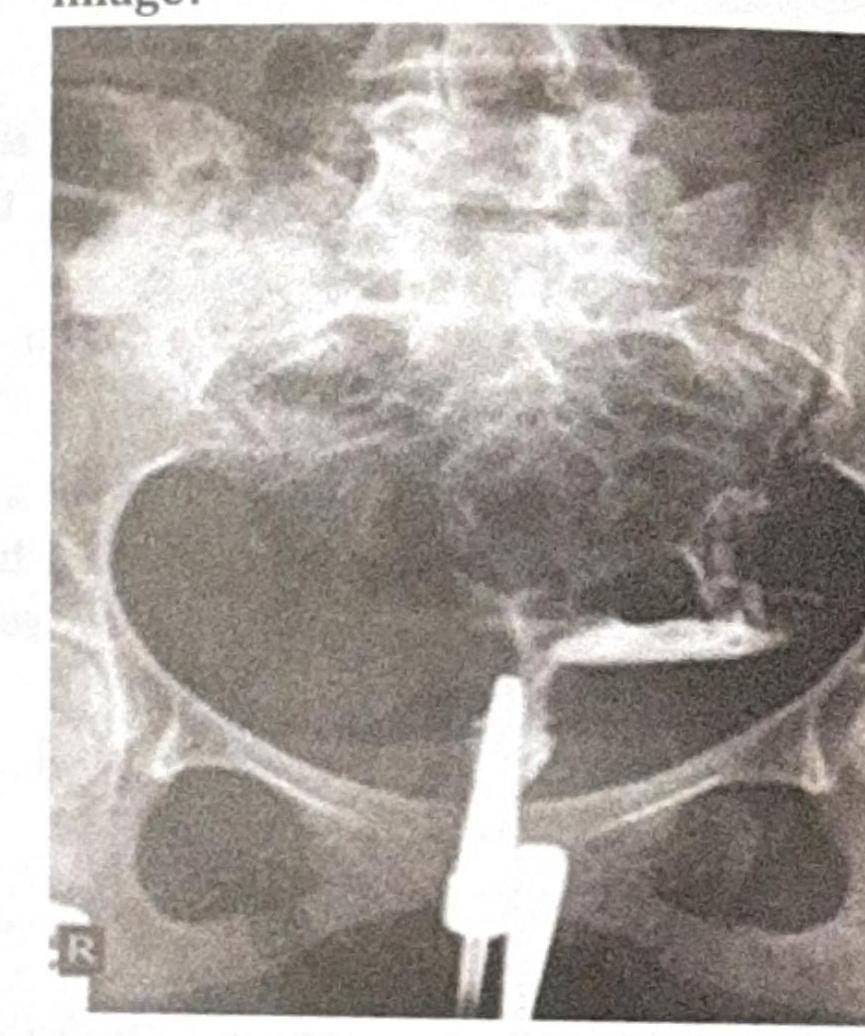

What is the modality of the test shown in the image?

Explanation: ***Hysterosalpingography*** - The image shows a **contrast-filled uterus and fallopian tubes**, characteristic of a **hysterosalpingogram (HSG)**. - An HSG uses **X-rays** and **radiopaque contrast media** to visualize the uterine cavity and assess fallopian tube patency. *Hysteroscopy* - **Hysteroscopy** involves direct visualization of the uterine cavity using a **fiber optic endoscope** inserted through the cervix. - It does not produce an X-ray image with contrast filling the fallopian tubes. *Laparoscopy* - **Laparoscopy** is a minimally invasive surgical procedure that involves inserting a **laparoscope** through an incision in the abdominal wall to view pelvic organs externally. - This image clearly depicts an internal view of the uterus and tubes through contrast, not an external, endoscopic view. *Saline infusion sonography* - **Saline infusion sonography (SIS)**, also known as sonohysterography, uses **ultrasound** imaging during the infusion of saline into the uterus. - While it assesses the uterine cavity, it is an ultrasound-based technique and does not involve X-ray contrast passing through the fallopian tubes, as seen in the image.